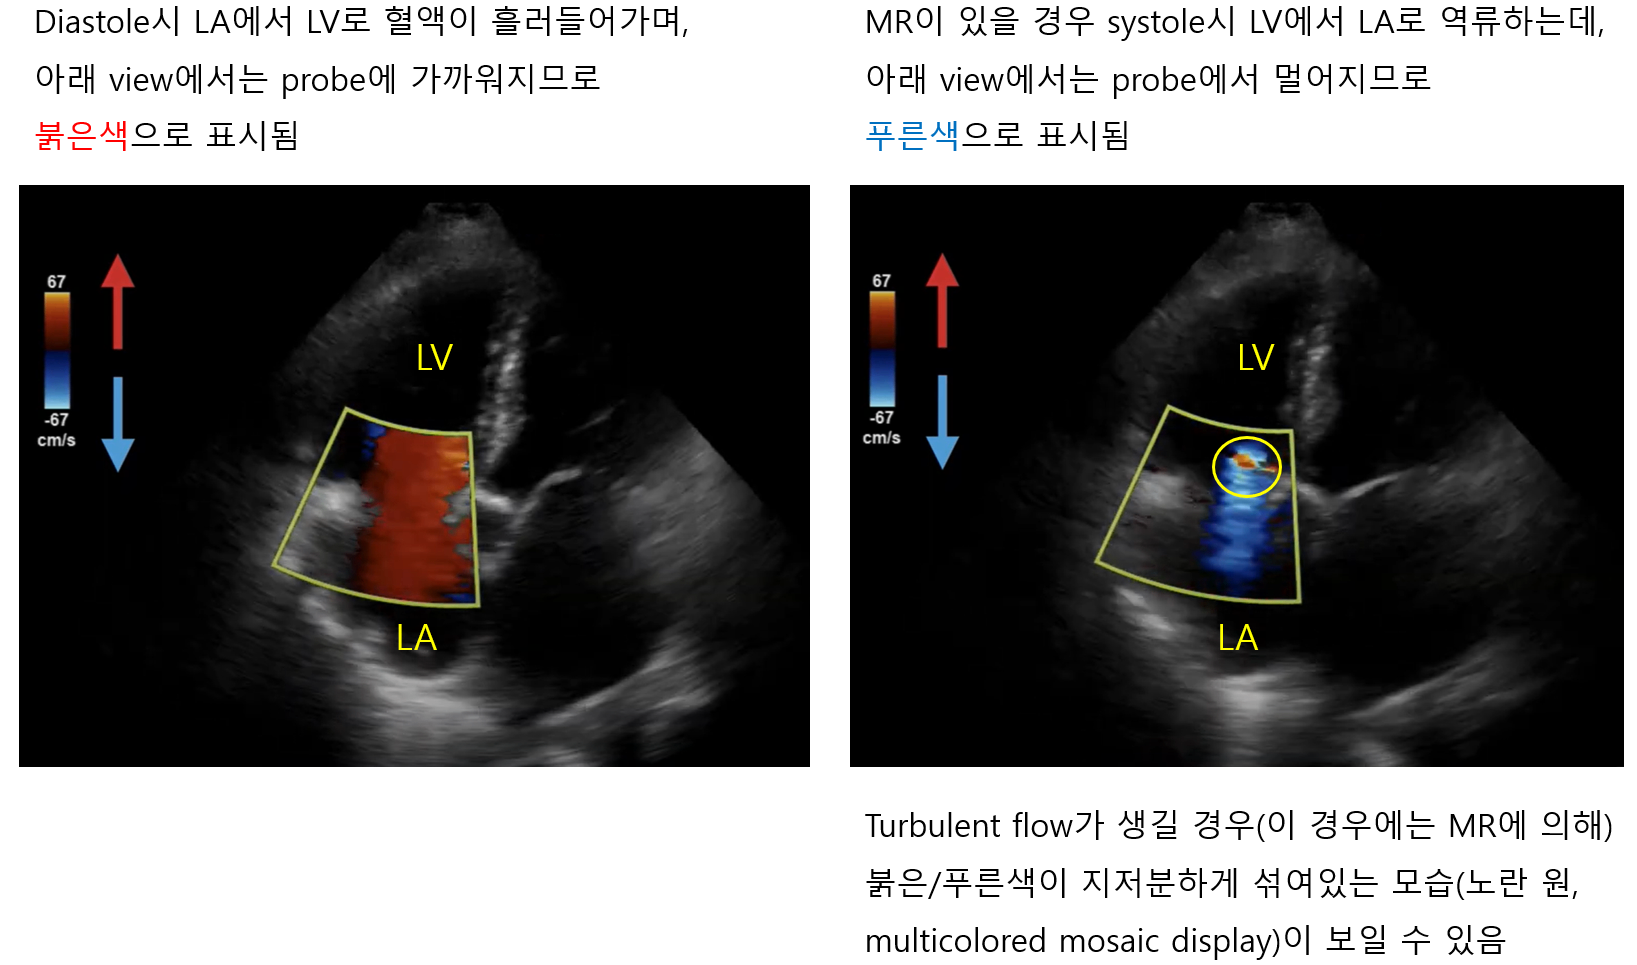

2) Color Doppler

(1) 2D 초음파 화면에서 해당 위치의 혈류가 probe를 향해 얼마나 빠르게 움직이는지 색으로 나타냄

(2) 붉은색: Probe에 가까워지는 혈류 / 푸른색: Probe에서 멀어지는 혈류

(3) Multicolored mosaic display: Stenosis, regurgitation, shunt의 발견에 유용

• Stenosis, regurgitation, shunt가 있어 turbulent flow가 발생할 경우, 혈류의 방향이 빠르고 다양해짐

• 이로 인해 일정한 색이 나타나지 않고 붉은색/푸른색/노란색 등이 모자이크처럼 지저분하게 나타남